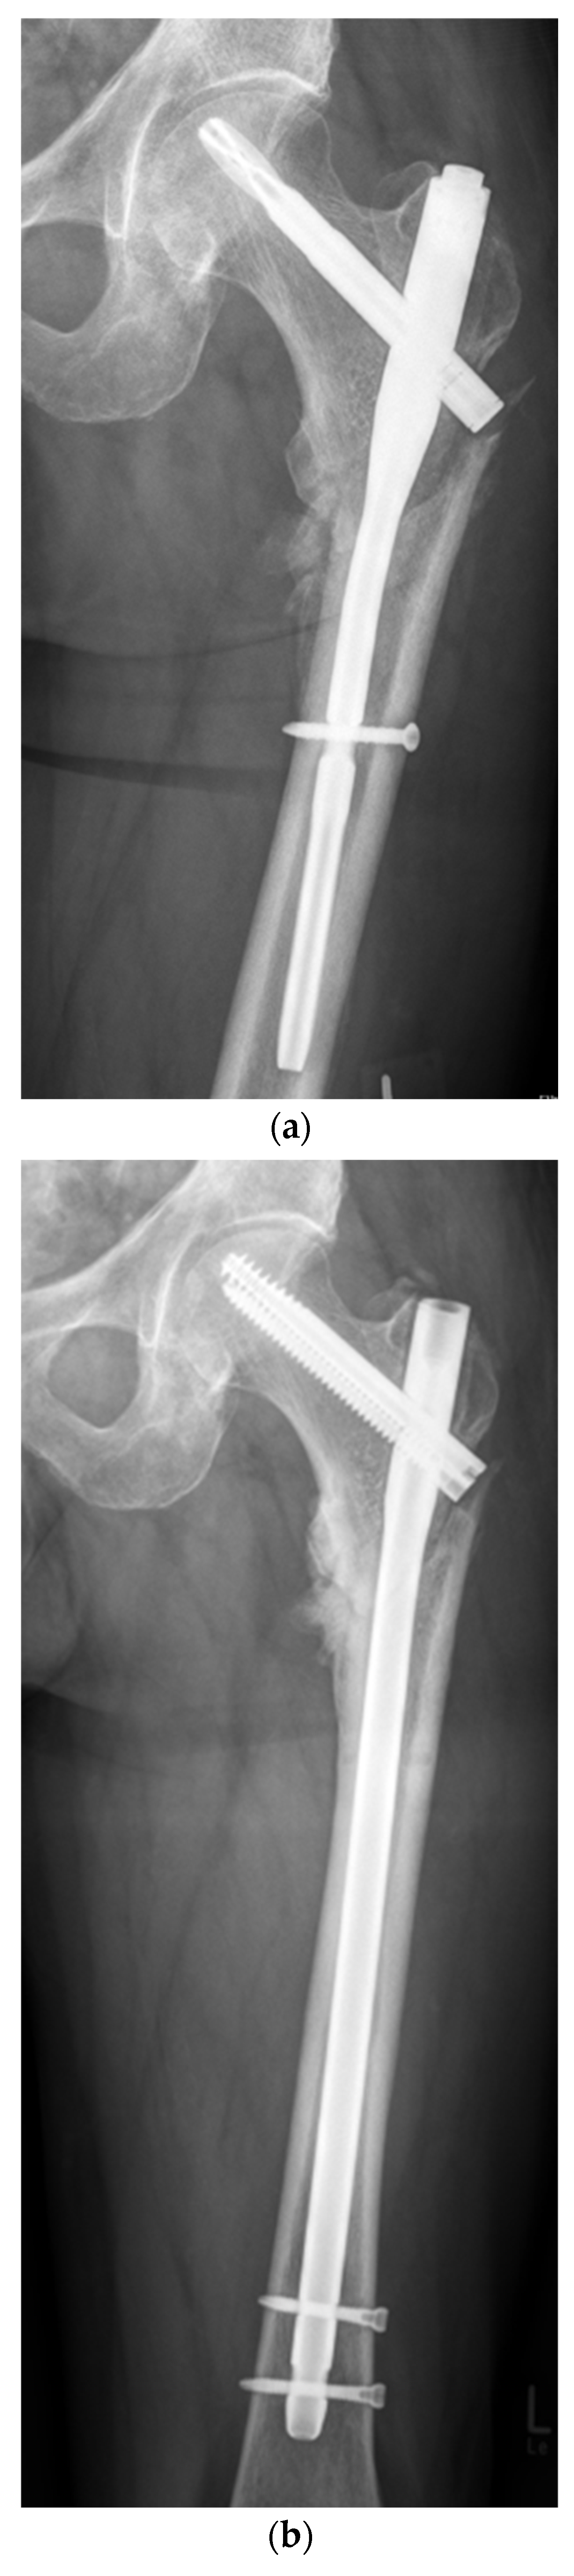

Functional and Radiological Results Following Revision Blade Plating and Cephalomedullary Nailing in Aseptic Trochanteric and Subtrochanteric Nonunion

2.2. Surgical Procedures